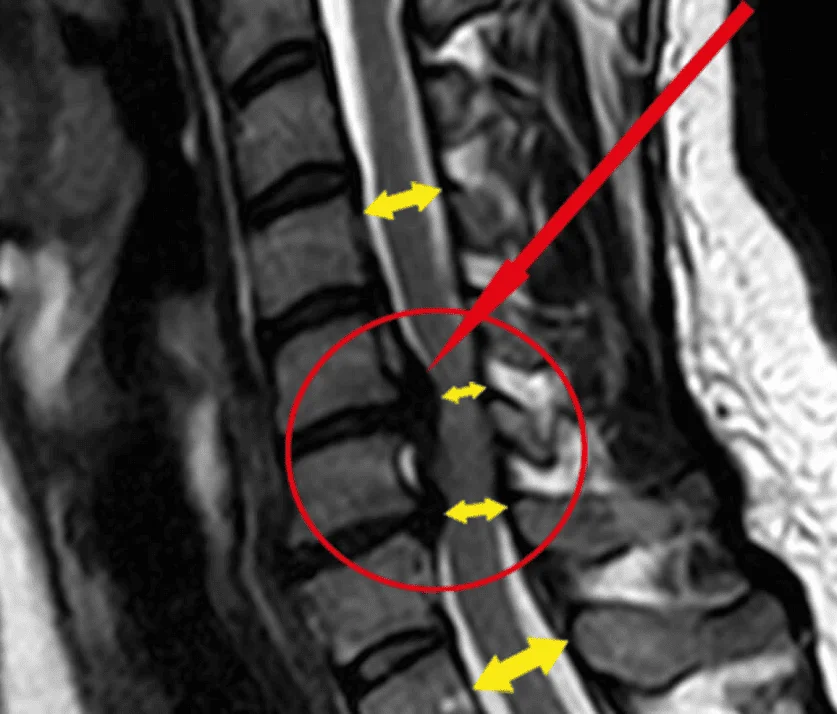

Dolor de cuello, dolor de espalda baja, discos herniados, neuropatía, carpal túnel,

ciática, lesiones (deportivas, caídas o accidentes), entre otras condiciones,

músculo esqueletales.